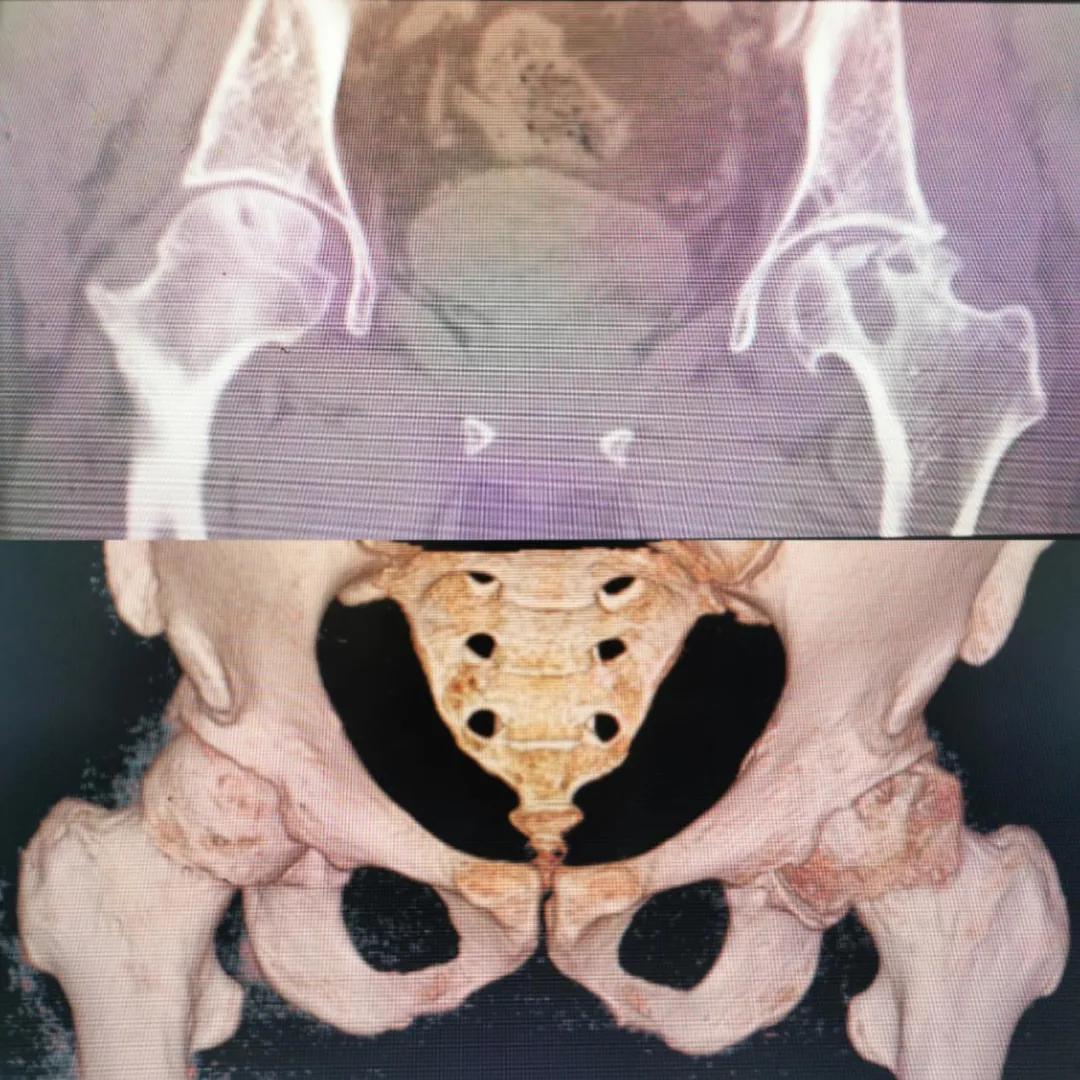

入院急查血結(jié)果提示炎癥反應(yīng),感染較重,凝血功能及肝功均不同程度損害;髖關(guān)節(jié)磁共振(MRI)檢查提示雙側(cè)股骨頭缺血壞死,繼發(fā)髖關(guān)節(jié)炎,左側(cè)髖周軟組織腫脹。醫(yī)療團隊給出的初步診斷為膿毒血癥、股骨頭缺血性壞死、軟組織感染、皮膚潰瘍及閉孔神經(jīng)損傷。

圖片(圖為患者入院時髖部CT檢查)

追溯病史,患者訴前不久曾用蜂蜇療法治療股骨頭壞死,每日4次,每次100只蜜蜂蜇雙臀部、髖部,這才導(dǎo)致了病情急劇進展。查明了來龍去脈,我院智能微創(chuàng)骨科醫(yī)護團隊與患者家屬積極溝通病情,給予特殊級抗生素抗感染以及消腫、止痛等支持治療,同時對潰瘍創(chuàng)面進行專業(yè)、規(guī)范的清創(chuàng)、換藥處理,保護創(chuàng)面降低感染程度;護理上輔助翻身,減少壓力性損傷。